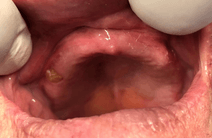

Why do I need to change the initial set?

For the first 6 months or so after placing your implants, we expect the gum to change shape. So after a while, your initial set won’t be a perfect fit.